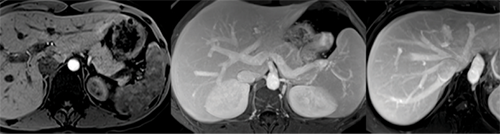

Hepatic arterial (left), portal venous (middle) and hepatic venous (right) anatomy displayed

Hepatic arterial (left), portal venous (middle) and hepatic venous (right) anatomy displayed in liver donor as part of a comprehensive liver donor protocol. All images courtesy of Kartik S. Jhaveri, MD.